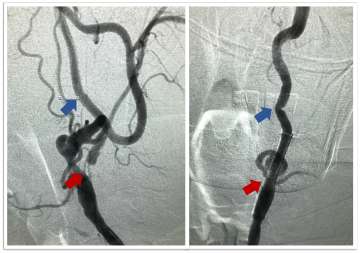

• Carotid Artery Stenting: This is a newer endovascular procedure performed from the inside of the blood vessels to open the stenosis. The surgeon uses small tubes and wires inserted into the wrist or groin arteries, navigated to the carotid artery in the neck. An umbrella is positioned above the narrowing to catch any debris and a stent is delivered to dilate the region of stenosis and hold the vessel open, improve flow and prevent future strokes (Figures 3 and 4).

Close-up angio images showing carotid stenting procedure with labeled arteries.

Figure 3. Carotid Stenting – Pre-treatment (left) cerebral angiogram image demonstrating severe cervical internal carotid artery stenosis (red arrow) before treatment and the relatively normal artery downstream (blue arrow).